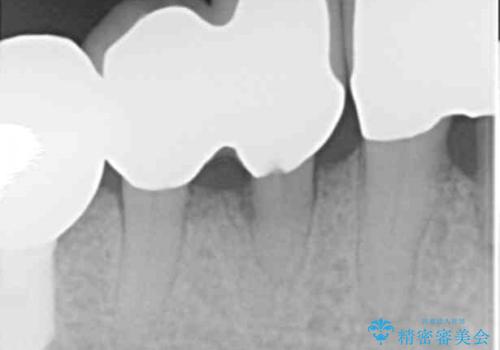

再生療法から1年後リエントリー手術により骨の再生を確認し、骨外科処置(骨を平らにして歯周ポケットの根本的な改善を図る処置)を行ったのち、連結補綴を行いました。

- ¥1,342,000 (再生療法、骨外科処置、部分矯正、仮歯×6本、クラウン×6本) ※税込費用は治療当時の料金となります

再生療法と骨外科処置により、歯周ポケットは全周2mm以下に改善されました。

生活歯(神経が生きている歯)のため形成量(歯を削合できる量)に限界がありましたが、熟練の技工士さんの素晴らしい技術により補綴を行うことができました。

クラウンの種類:メタルボンドクラウン エコノミー